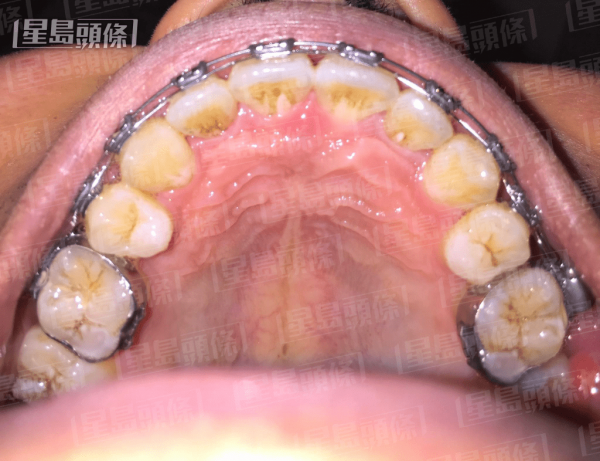

傳統箍牙方法。(牙科醫生胡瀚鈞提供)